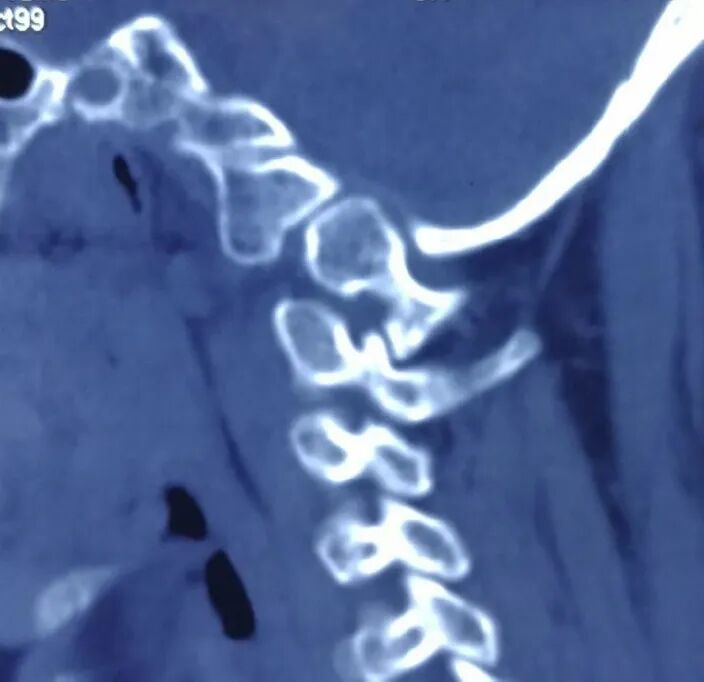

寰枢椎由3个关节构成:正中寰齿关节,两侧侧方关节。大多数寰枢椎脱位患者,特别是颅底凹陷合并的寰枢椎脱位患者,寰枢椎关节存在严重畸形,畸形的关节突发生严重的绞锁(图1),这导致寰枢椎脱位复位具有很大难度[1, 2]。